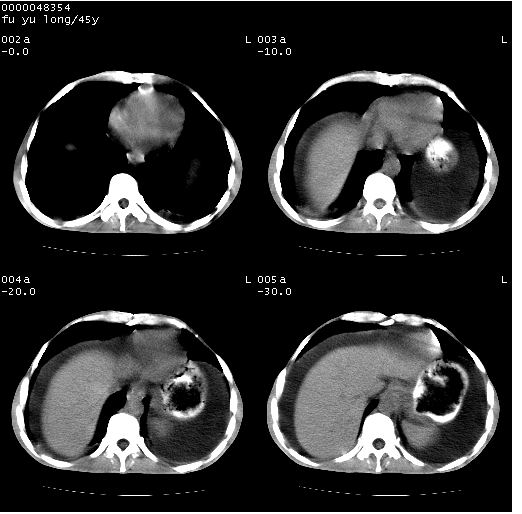

以下是引用lkc8963在2008-5-30 8:44:00的发言:[br]胃窦癌伴网膜(胃结肠韧带)/腹膜及腹膜后淋巴结转移.

以下是引用医影拾贝在2008-5-30 2:38:00的发言:[br]气肿性胃炎、胃十二指肠溃疡、腹膜炎,考虑穿孔可能性较大